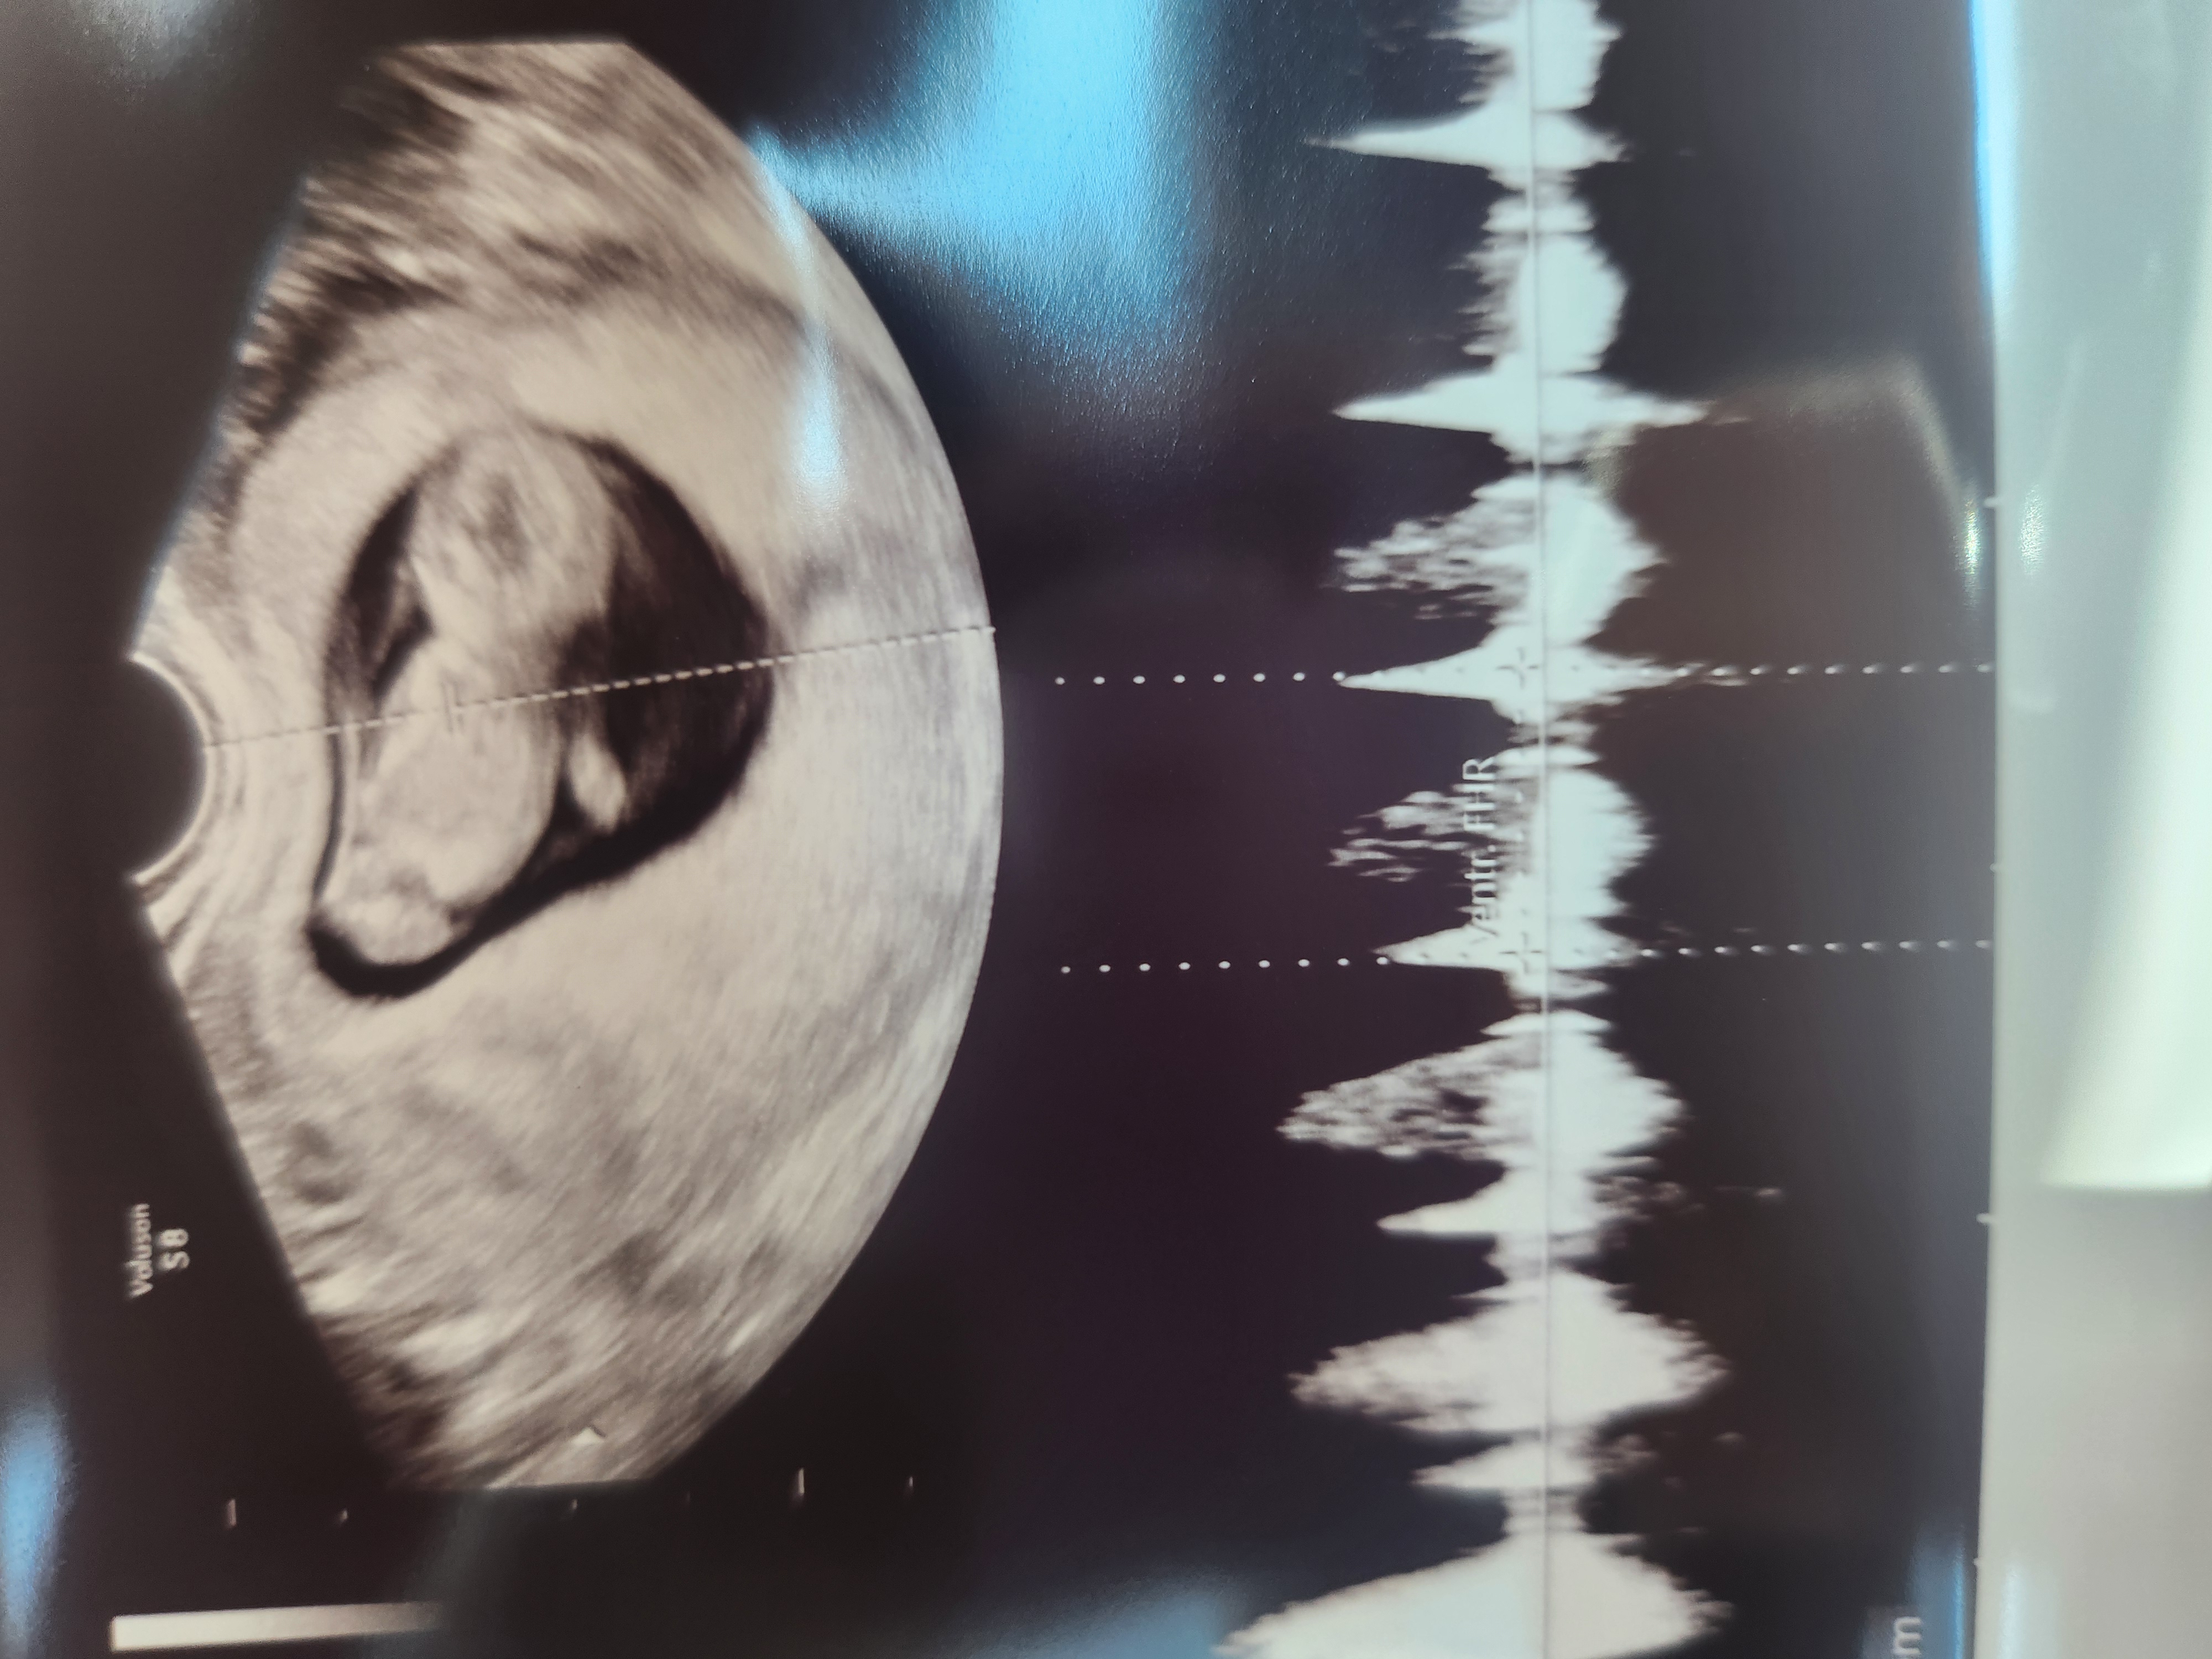

| 가슴 떨리는 임신 이야기를 공유해 주세요. | 드디어 6개월 만에 성공 소식을 듣고 졸업을 앞두고 있습니다. 성고 소식을 들었을때는 정말 너무 벅차고 믿기지 않을 만큼 감격스러웠어요. 기다림 끝에 찾아온 기쁨이라 더 크게 다가왔습니다. |